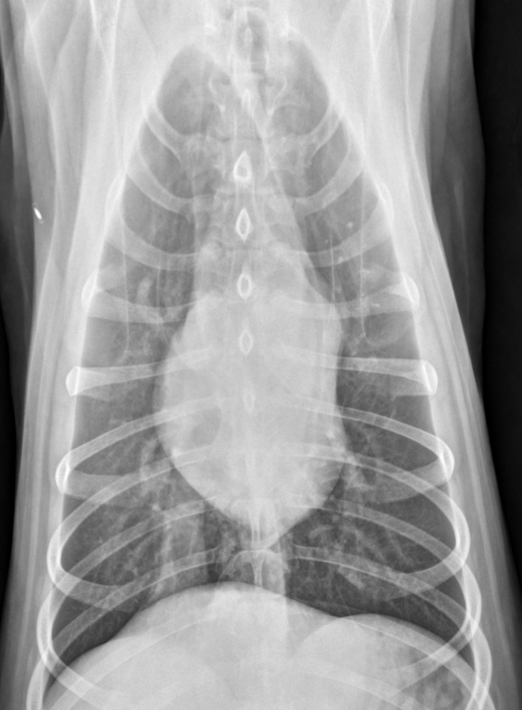

Lung Pattern?

Marked pleural effusion